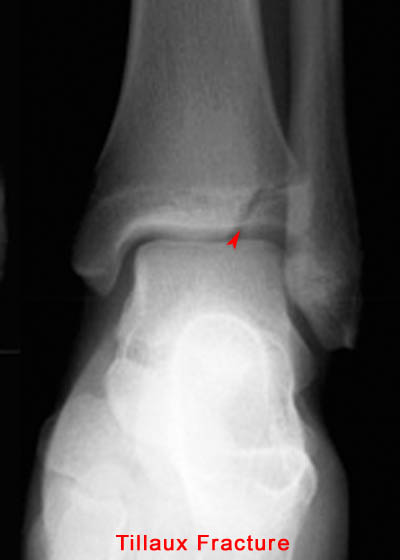

19) Name the abnormality shown in the image below.

20) In which demographic is the injury shown above most common? Adolescent Athletes

21) At which spinal level is the injury shown above most common? L5